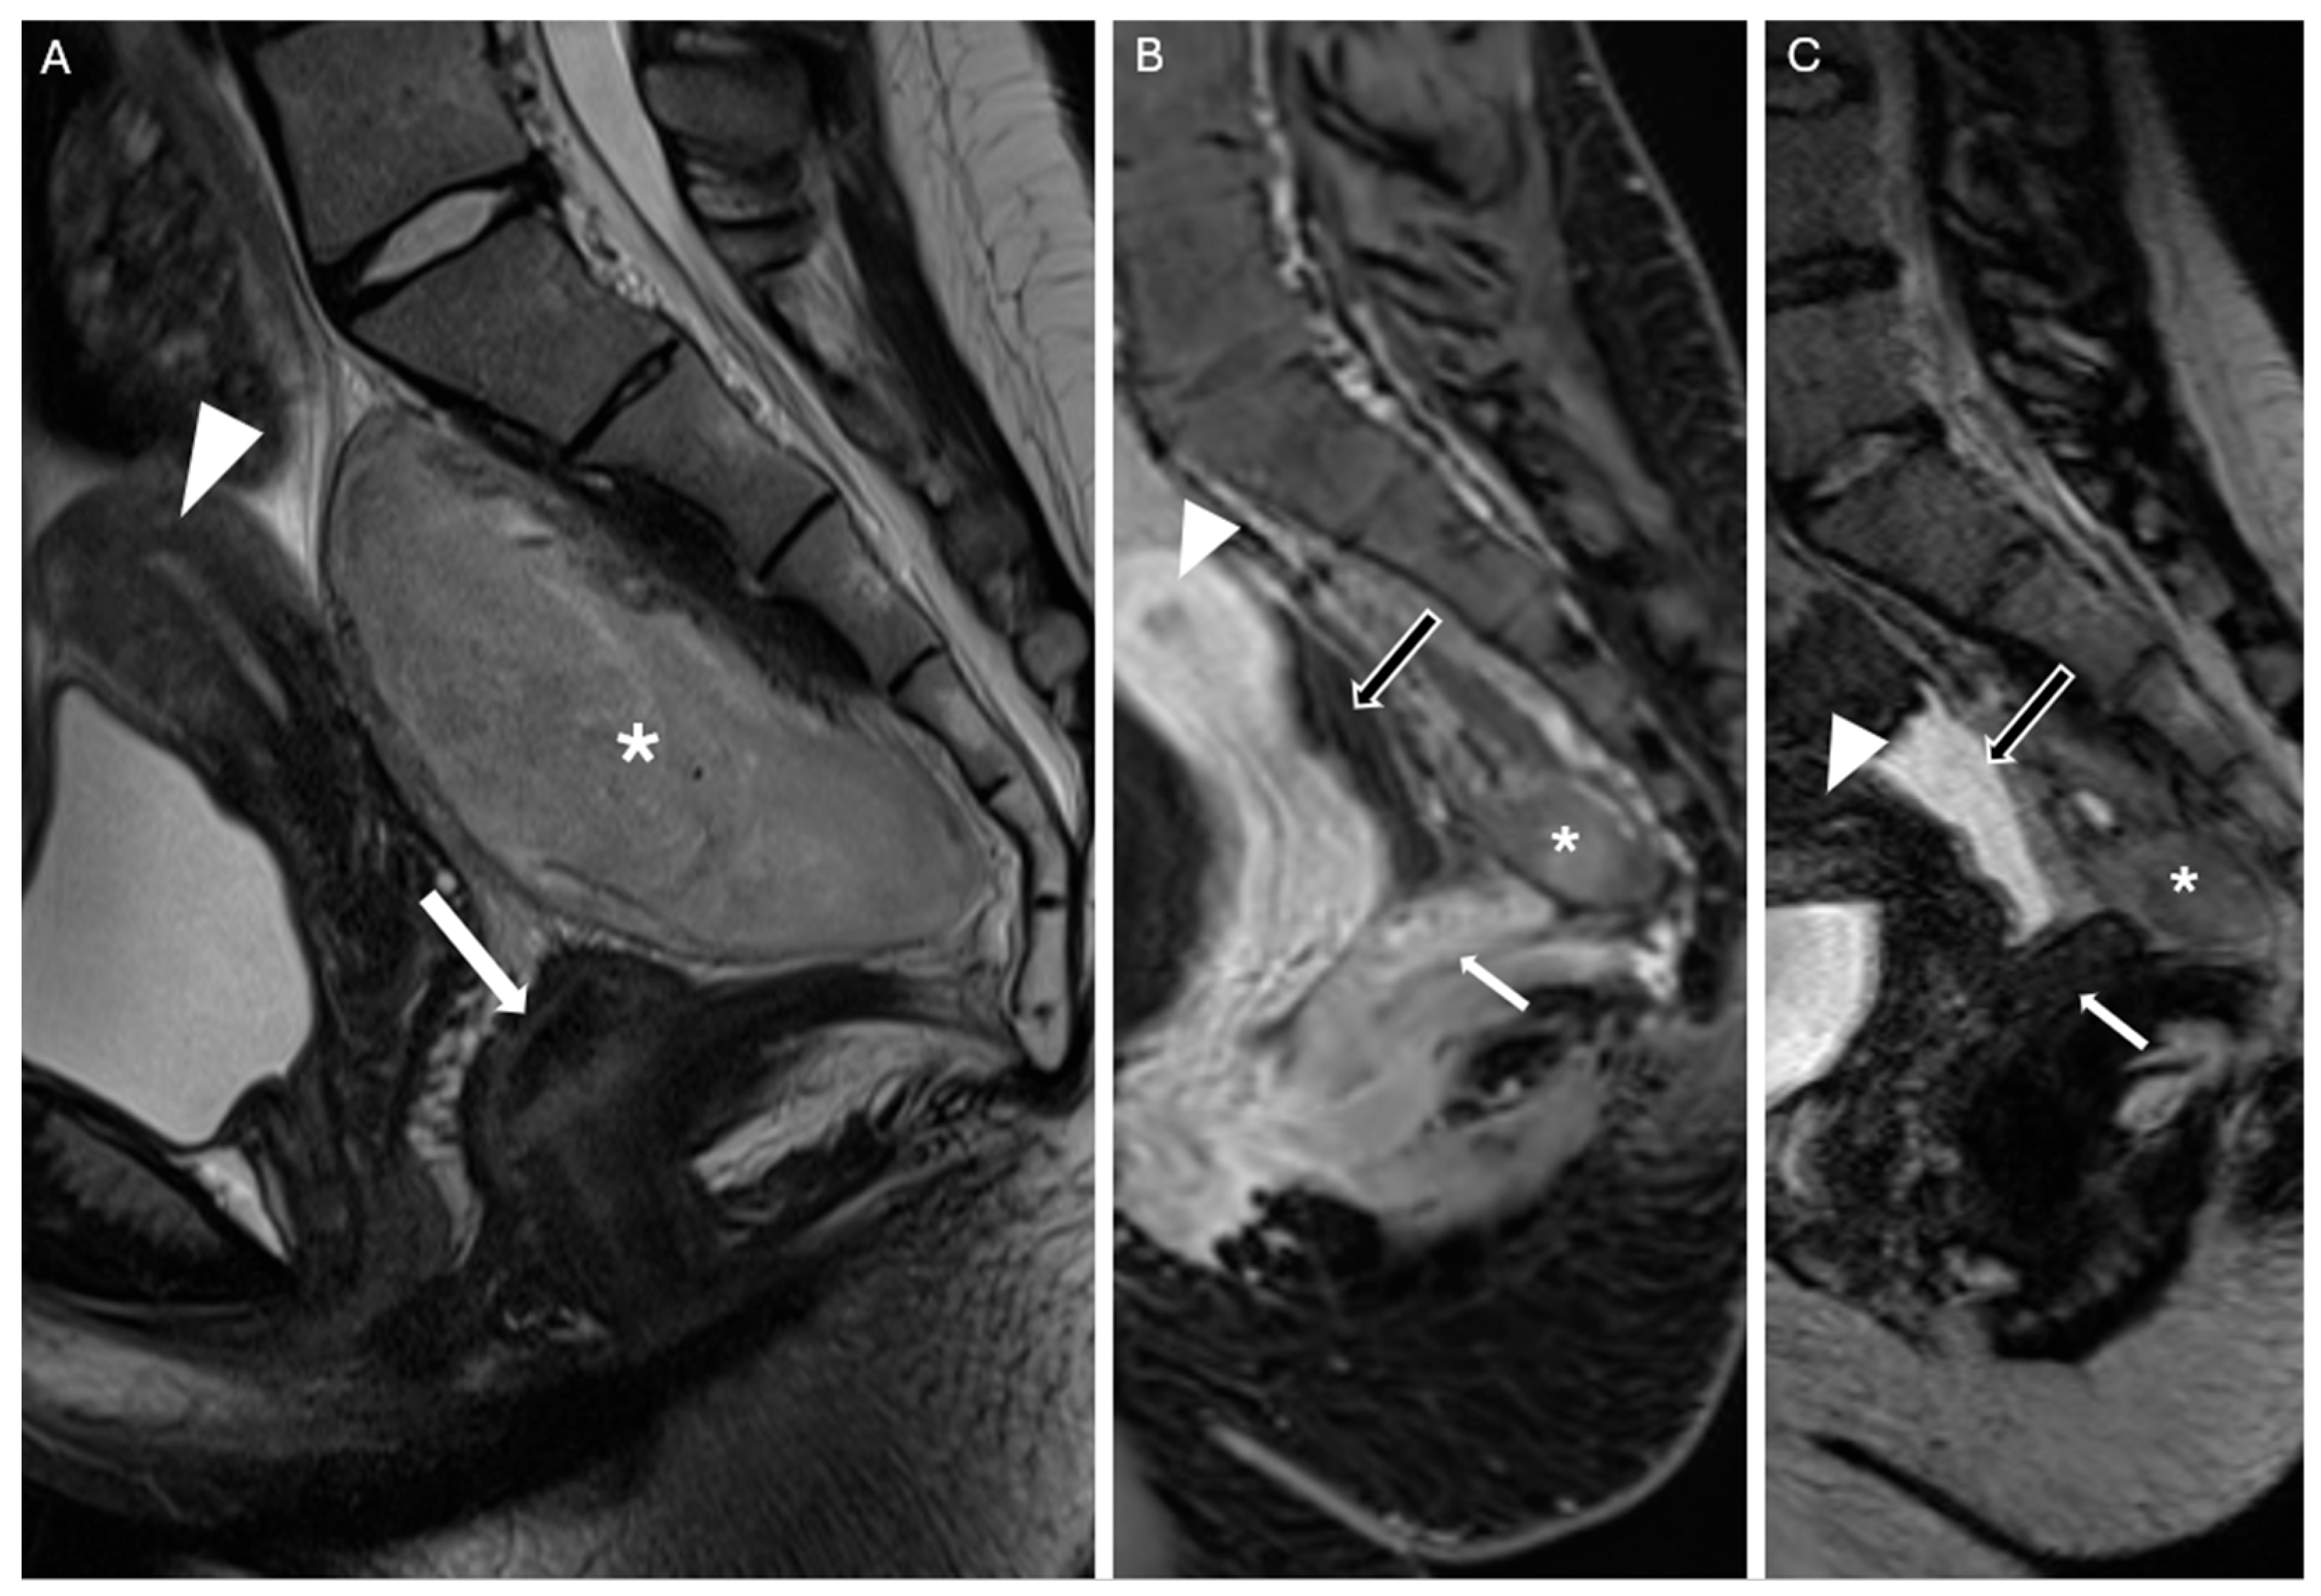

A follow-up contrast-enhanced MRI performed 30 days after surgery revealed a small residual lesion at the caudal portion of the surgical site, near the coccyx, consistent with remaining biological tumor tissue. In addition, a fluid-filled area was observed, likely related to the patient’s ovulatory phase and not indicative of pathological findings (Figure 7). No other pathological changes were observed. On the 30-day outpatient follow-up, the patient had resumed normal daily activities without pain or neurological deficits. A 3-month follow-up contrast-enhanced pelvic MRI was scheduled due to the benign nature of the tumor.

Figure 7. (A) Mid-sagittal TSE T2-weighted image from the preoperative MRI for comparison. (B) Postoperative contrast-enhanced MRI at 30 days: mid-sagittal T1 VIBE Dixon-enhanced image. A small residual portion of the neoplasm is visible anterior to the coccyx (white asterisk); the patient reported no symptoms during the outpatient follow-up. At the time of the MRI, the patient was in the ovulatory phase, which explains the presence of fluid in the Douglas pouch (black arrow with white outline). (C) Postoperative contrast-enhanced MRI at 30 days: same mid-sagittal view as in image B, T2 SPACE-weighted image. White arrowhead: uterus; white arrow: rectum.